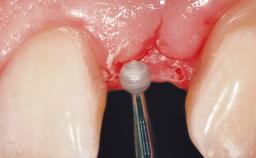

Immediate Flapless Placement of an Implant in a Maxillary Left Central Incisor Site

A 29-year-old female patient presented for treatment to replace the upper left central incisor tooth with an implant- supported restoration. The tooth had been intermittently symptomatic for the previous 12 months. The tooth had originally suffered trauma about 15 years previously. Several endodontic treatments had been performed, including an apicectomy procedure to retain the tooth. The patient was healthy and a non-smoker. She had reasonable expectations in regard to esthetic outcomes and the risk of marginal tissue recession following treatment. At medium smile, the gingival margins of the upper teeth were visible, with a display of 3 to 4 mm of the gingival margins. Gingival recession of tooth 21 and a discrepancy in the gingival levels between teeth 11 and 21 was observable during normal speech and smile.

Placement Protocol Immediate implant placement

Tooth Site Maxillary incisor or canine

Socket Morphology Single-root socket